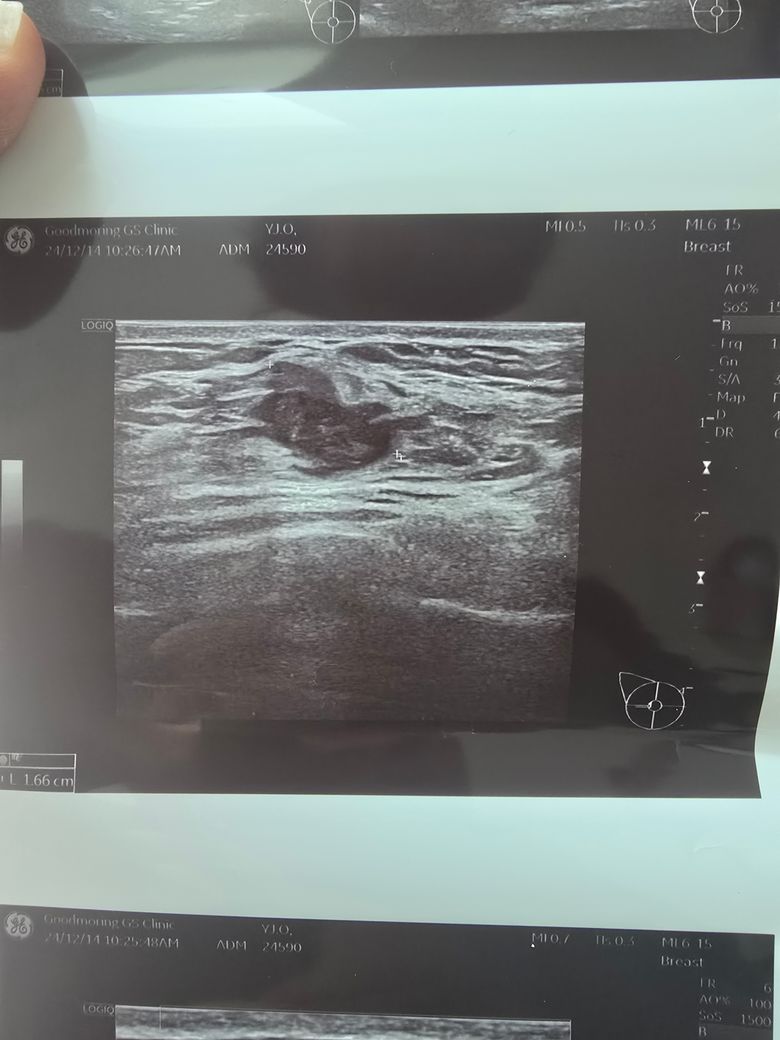

가슴부위 9시방향에 몽울잡혀 병원 방문, 초음파사진

선생님이 모양도 안좋고 림프절도 보이는것으로보아 암가능성이 많다고 조직검사하고 대학병원 알아보라고하셨는데 한편으로는 건강검진받은지 1년5개월정도 밖이 안되어서 림프절이붓는 가능성있지만 낮다고하시는데 선생님들 제발 한번만 봐주세요 부탁드립니다.

• 1번 째 사진

유방 초음파에서 관찰된 종괴의 내부 음영이 불규칙하고 주변 조직으로 침윤하는 모습이 관찰되며 림프절 비대까지 동반되어 있습니다. 이러한 상황이라면 악성 종양, 즉 유방암 가능성을 배제하기 어렵습니다.

건강검진 당시 특이사항이 없었다 하더라도, 유방암은 짧은 기간 내에도 발생할 수 있는 경우가 있어 현재의 초음파 소견과 임상증상(멍물 분비)을 더 중요하게 고려해야 합니다. 특히 종괴의 모양이 불규칙하고 경계가 분명하지 않으며 림프절 이상이 동반된다면, 조직검사를 통해 확진을 받는 것이 필수적입니다.